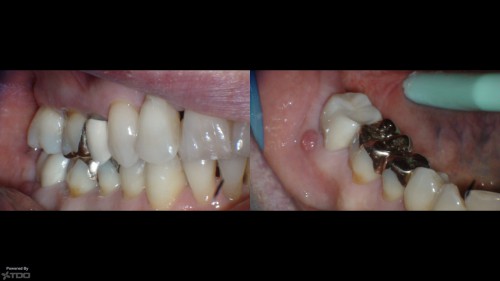

73yof in today for obvious reasons. I just can't figure this out…let alone why anyone […]